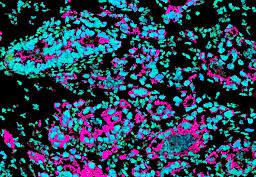

Pancreatic ductal adenocarcinoma is a lethal disease with limited treatment options and poor survival. We studied 83 spatial samples from 31 patients (11 treatment-naïve and 20 treated) using single-cell/nucleus RNA sequencing, bulk-proteogenomics, spatial transcriptomics and cellular imaging. Subpopulations of tumor cells exhibited signatures of proliferation, KRAS signaling, cell stress and epithelial-to-mesenchymal transition. Mapping mutations and copy number events distinguished tumor populations from normal and transitional cells, including acinar-to-ductal metaplasia and pancreatic intraepithelial neoplasia. Pathology-assisted deconvolution of spatial transcriptomic data identified tumor and transitional subpopulations with distinct histological features. We showed coordinated expression of TIGIT in exhausted and regulatory T cells and Nectin in tumor cells. Chemo-resistant samples contain a threefold enrichment of inflammatory cancer-associated fibroblasts that upregulate metallothioneins. Our study reveals a deeper understanding of the intricate substructure of pancreatic ductal adenocarcinoma tumors that could help improve therapy for patients with this disease.